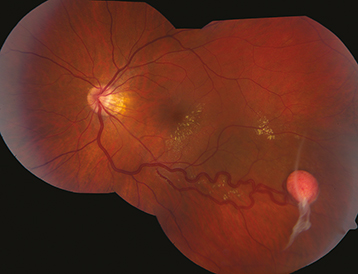

Figure 13.11.4: Retinal astrocytic hamartoma.

Rapuano9781975243722-ch013_f008.jpg

Astrocytic hamartoma of the retina or optic disc (a white, semitransparent, or mulberry-appearing tumor in the superficial retina that may undergo calcification with age; no prominent feeder vessels; no associated retinal detachment; often multifocal and bilateral) and punched-out chorioretinal depigmentation.